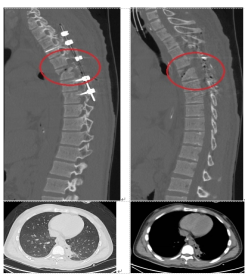

在麻醉科、胸外科、输血科、重症医学科等多科室的配合下,患者于2024年07月18日由骨科吴俊一主任医师主刀、宿瑞强主治医师、黄孝明主治医师等配合下,在全麻下进行了“经后路胸6椎体骨折、胸5/6椎脱位切开复位胸3-8钉棒系统(8钉2棒)内固定术+胸5-6椎管扩大减压+硬脊膜修补术+自体骨、人工骨椎板后、关节突植骨融合术”。术前胸外科先行“双侧胸腔闭式引流术”。术后转入重症医学科重症监护治疗。术中使用了关键设备——超声骨刀,为脊柱椎管扩大减压大大节省了时间,止血彻底;术中同时使用了另一神器,可谓“千里眼”的“C臂X光机”,为手术安全性提供了强有力的保障。

经过31天的精心治疗与护理,患者顺利出院。此次胸椎手术置钉达到胸3水平,体现阿坝州人民医院脊柱手术突破新高度。压疮的积极防治亦体现了州人民医院骨科在加速康复外科治疗的努力。